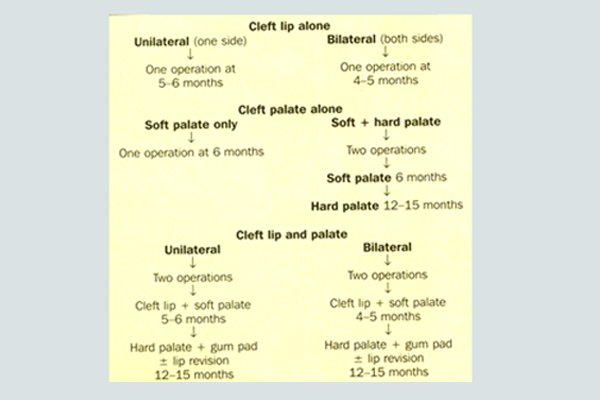

Ideal treatment is 3-6 months for cleft lip patients and 9-18 months for cleft palate Patients.

Surgical treatment called palatoplasty and Cheiloplasty are carried out on babies from the age of 3 month to 12 months [ Uk ], 6-14 month [ USA ], EU 3-17 Months and India 3-18 Months.